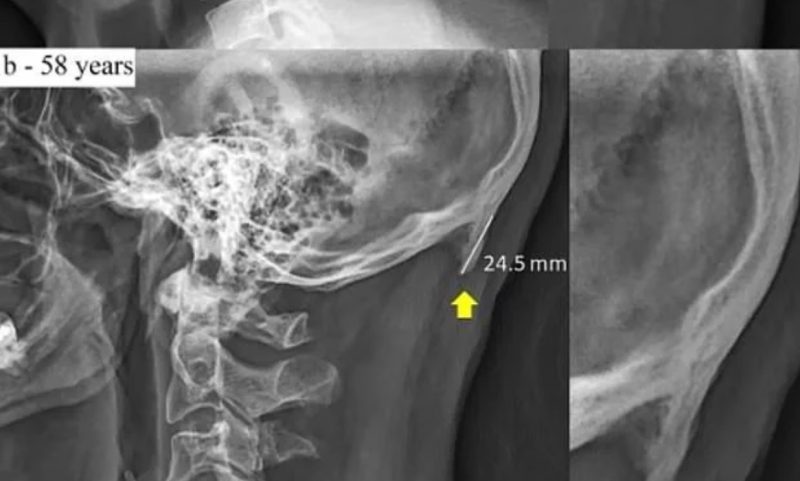

Pasar tanto tiempo con la mirada hacia abajo produce tal cambio en la postura que nuestra estructura ósea trata de adaptarse para sostener mejor nuestra cabeza. La prueba está en las imágenes de rayos X publicadas por investigadores australianos que muestran que debido a la forma en que estamos constantemente encorvados con nuestros teléfonos, los cráneos desarrollaron un crecimiento óseo adicional. La cabeza de adulto promedio puede pesar alrededor de 5 kilogramos.

Según el estudio, un número creciente de personas, especialmente los jóvenes de entre 18 y 30 años, tienen crecimientos llamados protuberancias occipitales externas agrandadas, que se encuentran en la parte inferior del cráneo. “Los trastornos musculoesqueléticos relacionados con la mala postura durante el uso de computadoras y tablets se investigaron de forma exhaustiva y se identificaron como un factor de riesgo para el desarrollo de síntomas relacionados en el cuello, los hombros y los antebrazos “, argumentan.